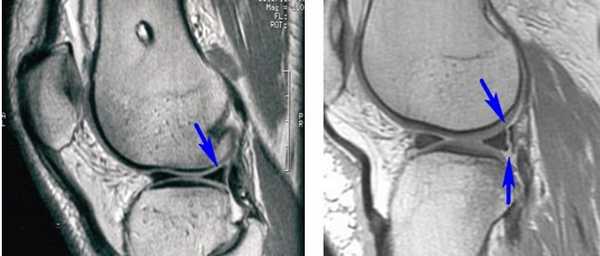

1. Диагностическая артроскопия проводится для оценки выраженности внутрисуставных изменений и подготовки внутрисуставных структур для запланированного вмешательства, например, в случаях, когда после предшествующей артроскопии или другой диагностики коленного сустава уже прошло достаточно много времени

2. В ходе диагностической артроскопии подтверждается наличие дефицита (или недостаточности мениска) после выполненной ранее субтотальной или тотальной менискэктомии, оценивается выраженность вторичных хондральных изменений, которые также могут потребовать лечения, особенно в случаях, когда первичное вмешательство на коленном суставе выполнялось в другом учреждении или другим хирургом (рис. 3).